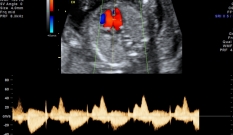

O rastreamento genético no segundo trimestre é feito com 15 semanas. São medidos, no sangue, os níveis de dois hormônios (beta-hCG, AFP, estriol não conjugado e inibina A). Se o risco é alto, será recomendada à paciente a realização de uma amniocentese para confirmar o diagnóstico.